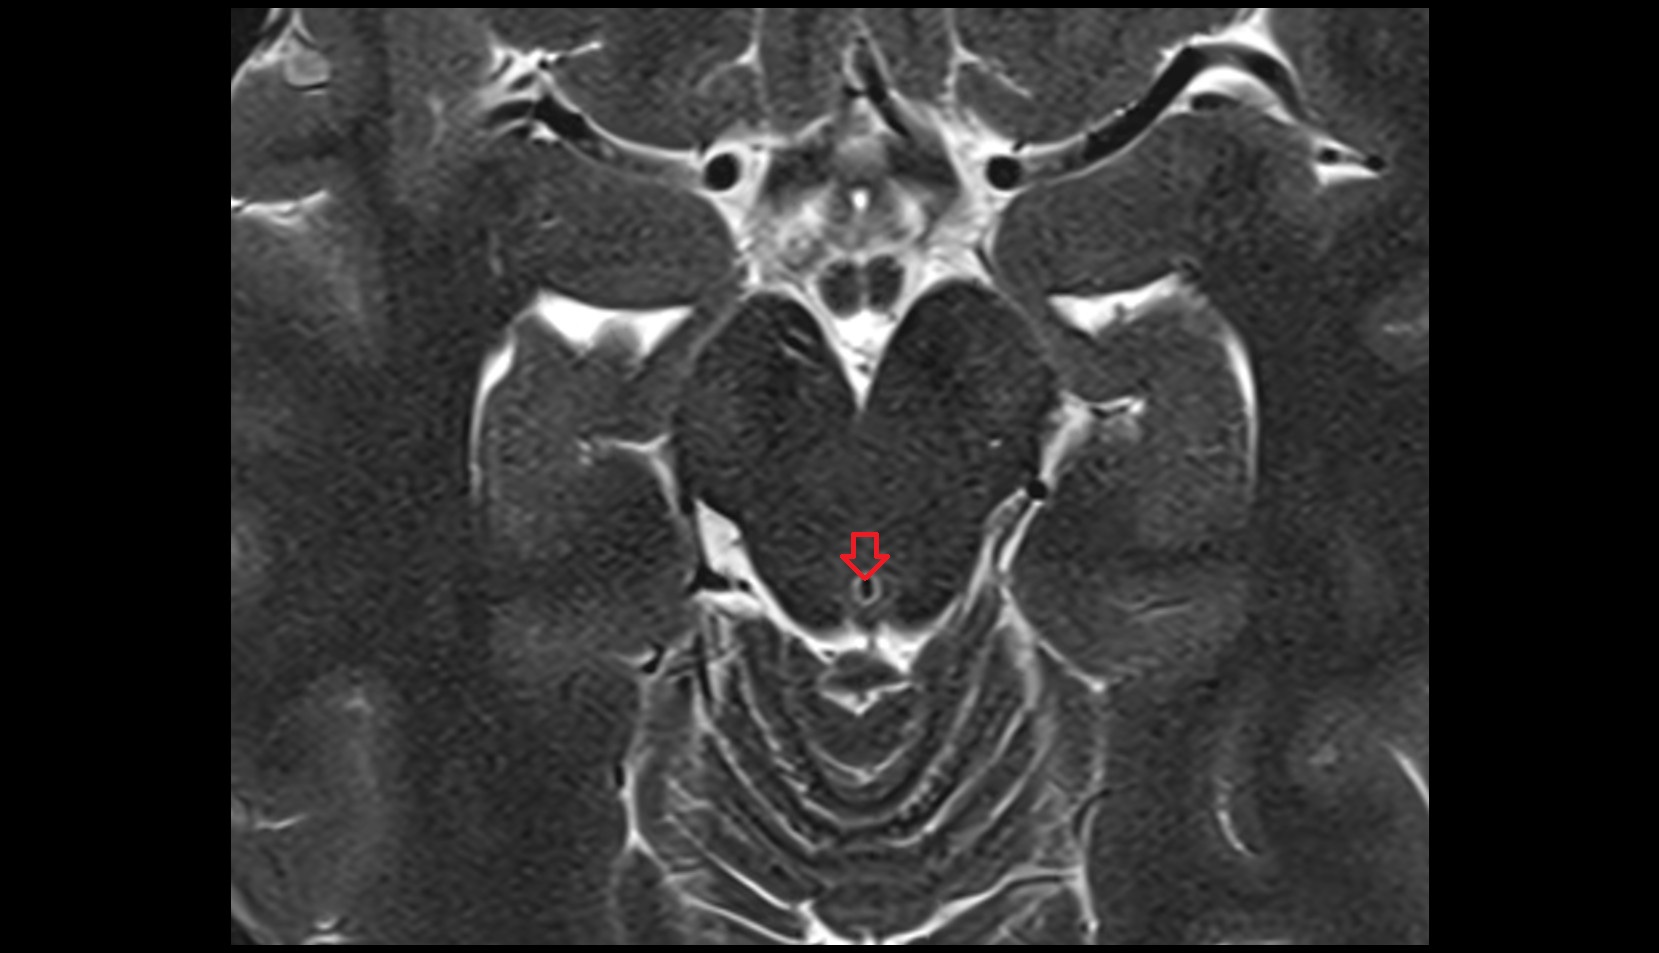

- Fourth ventricle

- Median aperture of fourth ventricle (foramen of Magendie)

- Median sulcus of rhomboid fossa

- Median aperture of the fourth ventricle

- Obex